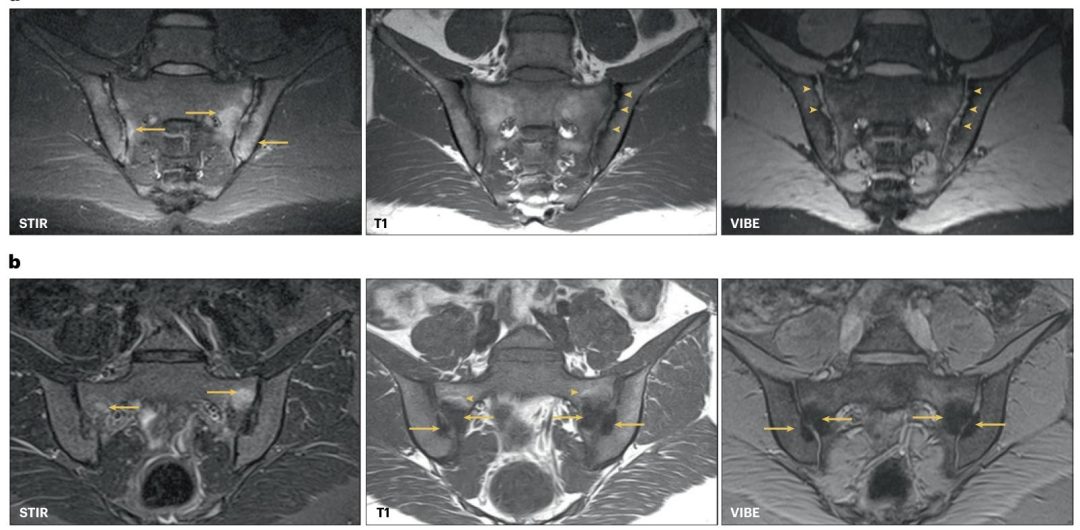

在中轴型脊柱关节炎中,炎症主要累及骶髂关节软骨间隙中部,并会相对快速地(在数月内)导致中轴型脊柱关节炎特异性结构性病变 —— 侵蚀和回填(表现为侵蚀腔内修复组织的脂肪信号)。图 1 展示了骶髂关节炎症性(中轴型脊柱关节炎)和机械性(髂骨致密性骨炎)改变的示例。要区分中轴型脊柱关节炎与机械性或退行性背痛,需采用合适的成像协议。国际脊柱关节炎评估协会 - 脊柱关节炎研究与治疗网络(SPARTAN)的成像建议主张采用标准化的四序列 MRI 协议。

图1:中轴型脊柱关节炎与髂骨致密性骨炎患者骶髂关节的典型MRI改变模式

a. 中轴型脊柱关节炎模式:左侧骶髂关节软骨间隙中部出现软骨下骨髓水肿(短 tau 反转恢复序列(STIR)箭头所示),并伴有侵蚀(T1加权成像和容积内插呼吸门控序列(VIBE)箭头所示)。VIBE序列能更清晰地显示较小的侵蚀灶。

b. 髂骨致密性骨炎的机械性诱导改变模式:双侧骶髂关节前部出现骨髓水肿(STIR序列箭头所示),伴有大量硬化(T1加权成像和VIBE序列箭头所示),以及部分脂肪化生(T1加权成像箭头所示)。无侵蚀性损伤。